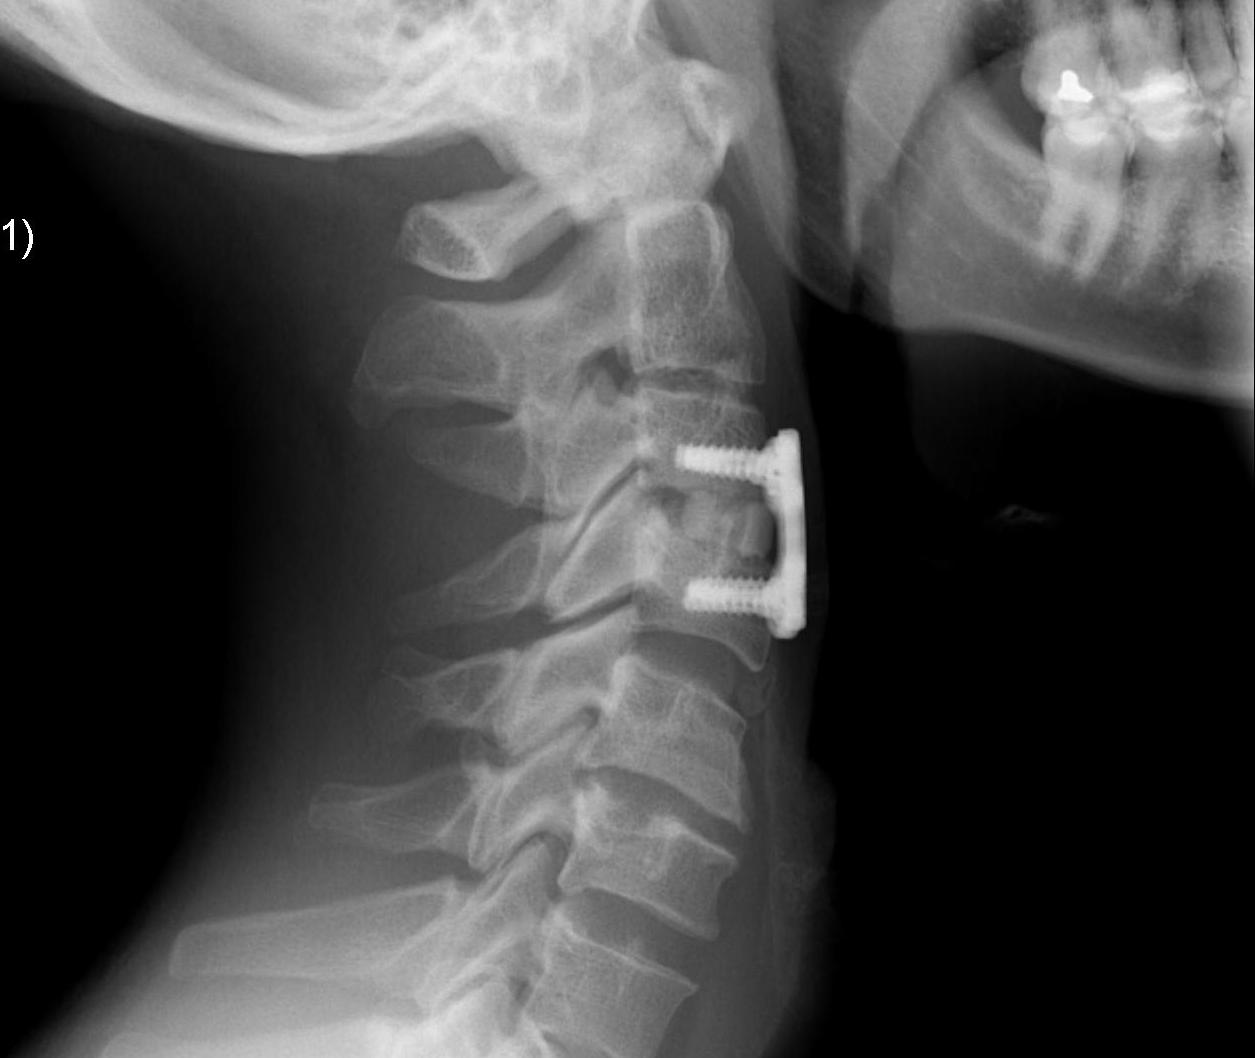

ACDA / Disc replacement

Advantage

Theoretically maintain some motion and preserve other disc segments

Technique

Depuy Discover Medtronic Prestige

Complications

Specific

- anterior displacement

- posterior displacement and spinal cord injury

- subsidence 3% - higher risk if remove or disrupt end plates

- osteolysis

- implant failure

- heterotopic ossification